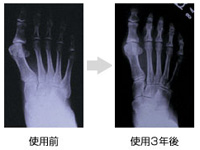

インソール療法とは、それぞれの患者様の足に合わせてオーダーメイドのインソール(足底板)を製作し、普段の歩行時に継続的に履いていただくことで身体のバランスを整えていく治療です。リハビリ治療、スポーツアスリートのトレーニング現場などでも積極的に取り入れられています。

治療に使うインソールは、体重を支える関節などに問題があって足やヒザ、股関節などが痛む場合にその症状や状態に応じて製作され、「偏平足なら土踏まずを持ち上げる」とか「あたる所、タコがある所の負担を減らす(圧力を分散させる)」ことにより、無理な歩行姿勢から生じる疲れや痛みを取り除く役割を果たします。

インソールを使っていただくと身体のバランスや筋肉の付き方が変わってきます。それに応じて歩き方も変化するので定期的なインソールの調整が必要となってきます。当院ではその経過を診断し、継続的に調整・治療を行います。